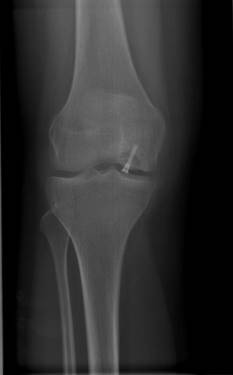

Die Röntgenaufnahme des Knies zeigt den Knochendefekt nach Ablösung des Dissekats. © Gelenk-Klinik

Das betroffene Kniegelenk wird in 2 Ebenen geröntgt. Dabei werden eine a.-p. Aufnahme (anterior-posterior, d. h. der Strahlengang verläuft von von vorne nach hinten durch das Kniegelenk) und eine seitliche Aufnahme des Kniegelenks angefertigt. Das Röntgen sollte unter Belastung des Gelenkes erfolgen, das heißt der Patient steht bei den Aufnahmen. Erst bei fortgeschrittenem Knochensterben (Nekrose) wird Osteochondrosis dissecans im Röntgenbild sichtbar. Dennoch ist eine indirekte Beurteilung des Knorpels im Kniegelenk möglich. Ist der sichtbare Gelenkspalt im Kniegelenk bei der Aufnahme im Stehen eingeengt, deutet dies indirekt auf eine abnehmende Festigkeit und Menge des vorhanden Knorpels hin. Die Röntgenaufnahmen können auch eine bestehende Achsfehlstellungen der Beine darstellen.

Die Röntgenaufnahme des Knies zeigt die Refixation eines abgelösten Knorpel-Knochen-Fragments. Dies kann mittels Titanschrauben (wie dargestellt) oder resorbierbarer Schrauben erfolgen. © Gelenk-Klinik